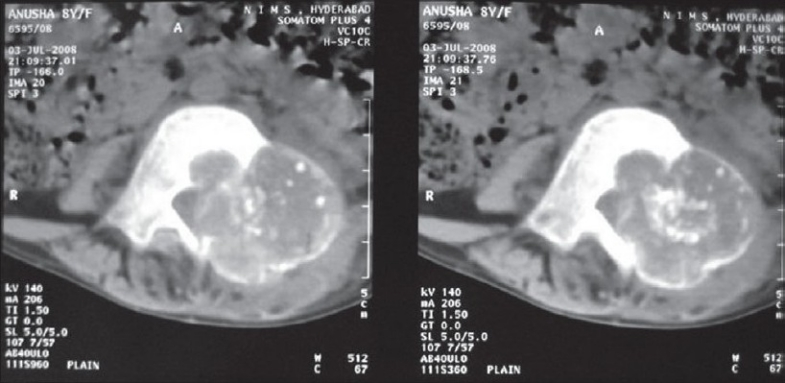

4.3 Tomografía computarizada (TC)

- 🩻 Es la técnica de elección para la planificación quirúrgica, especialmente en la columna vertebral.

- 🩻 Confirma la extensión de la lesión, la integridad cortical y la relación con estructuras neurales.

- 🩻 Evalúa la presencia de matriz calcificada.

Hallazgo radiológico característico